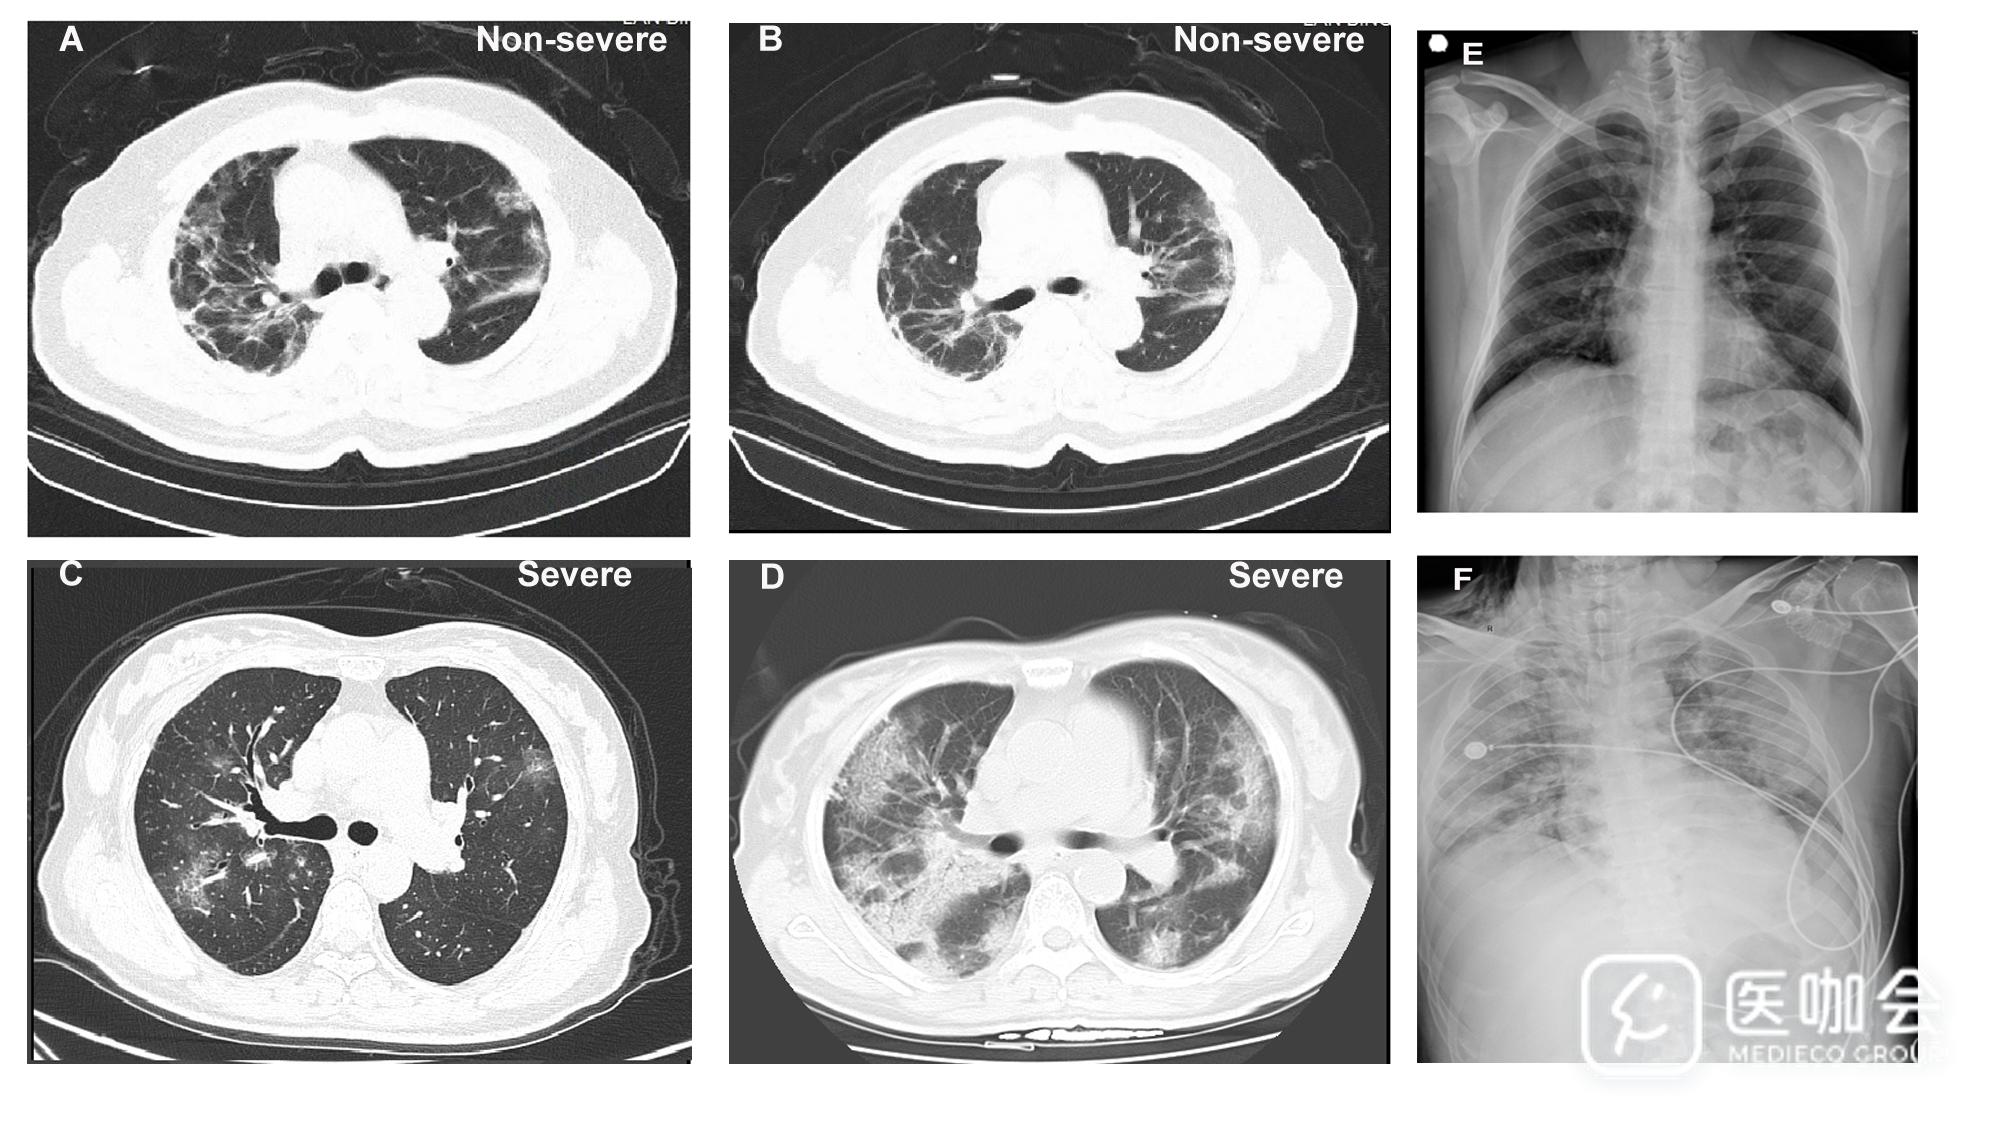

图E1(下图)展现了2名非重症组患者和2名重症组患者的影像学信息。重症组926例中有221例,非重症组173例中有9例患者的影像学特征并不明显,这些患者是通过症状结合RT-PCR阳性结果来确诊的。比起非重症组患者,重症组病例更易展现出胸片和胸部CT结果的异常情况(所有P<0.05)。

图E1

从临床表现来说,重症及非重症病例中分别有23.9%和5.2%在最初没有表现出胸部影像的异常。鉴于存在无明显影像学异常表现的确诊病例,以及20.9%的患者在发生肺炎之前或无肺炎时已分离出2019-nCoV,研究提出肺炎不是纳入临床表现所必须的,从而提出了“2019-nCoV ARD”这一术语,将无明显肺部影像学异常但实验室确诊的有症状病例纳入进来,并呼吁将重心转移到疾病进展前的早期发现和管理上。